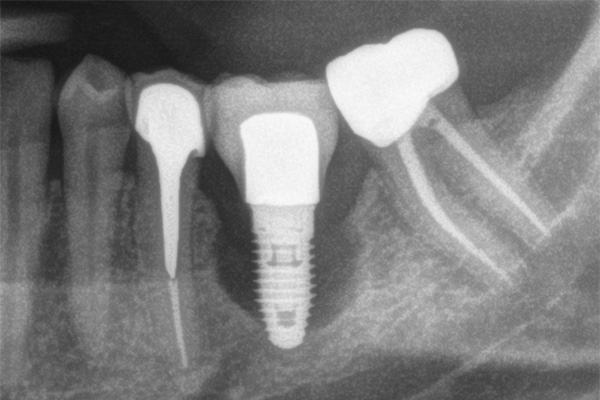

اگر رزوه (پیچ فلزی) ایمپلنت از لثه بیرون زده باشد (مانند عکس زیر)، یعنی استخوان اطراف تحلیل رفته و عفونت پیشرفت کرده است.

دندانپزشک با استفاده از معاینه بالینی و عکس رادیوگرافی (X-Ray) می تواند وجود عفونت یا تحلیل استخوان را تشخیص دهد.

گاهی برای تشخیص دقیق تر، ممکن است از اسکن سهبعدی (CBCT) نیز استفاده شود تا میزان آسیب به بافت و استخوان مشخص شود.

نقش عکس عفونت ایمپلنت در تشخیص

گاهی دندانپزشک برای بررسی دقیق تر از عکس رادیوگرافی یا سی تی اسکن فک CBCT استفاده می کند تا میزان تحلیل استخوان و موقعیت ایمپلنت مشخص شود. این تصاویر به شناسایی زودهنگام عفونت و جلوگیری از آسیب بیشتر کمک می کند.